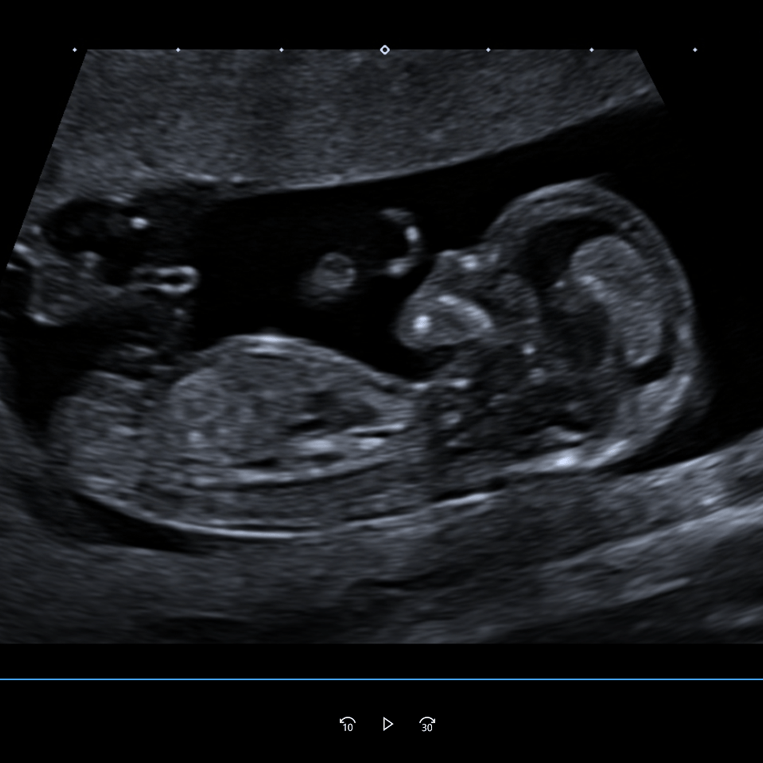

Schwangerschaft

Während der Schwangerschaft treten häufig viele Fragen auf. Daher ist es umso wichtiger, dass Sie sich gut aufgehoben und fundiert beraten fühlen.